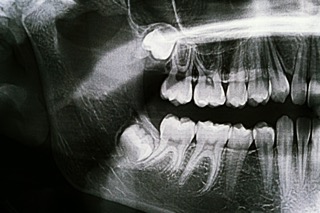

As we age, the jawbone becomes denser and less flexible, which can make adult wisdom tooth extraction slightly more complex. Additionally, roots are fully developed and may sit closer to nerves, increasing considerations such as nerve damage risk wisdom teeth procedures must account for. However, with advanced imaging and surgical expertise, safe outcomes remain highly achievable.

While risks like infection or nerve sensitivity may be slightly elevated, they are still uncommon when the procedure is performed by an experienced provider. Careful planning helps reduce concerns such as nerve damage risk wisdom teeth removal may present in more complex cases.